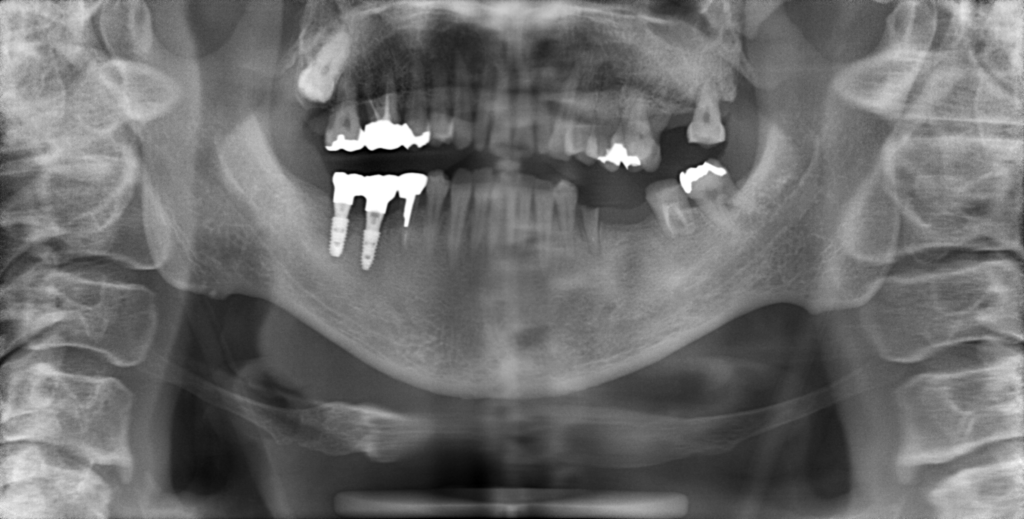

Y様インプラント実例 #44

左の上下の奥歯をインプラントで治療しています。

左下の奥歯は歯を抜くのと同時にインプラントの埋め込みを行っています。

被せものは上下、セラミックスで作っています。

治療前

治療後